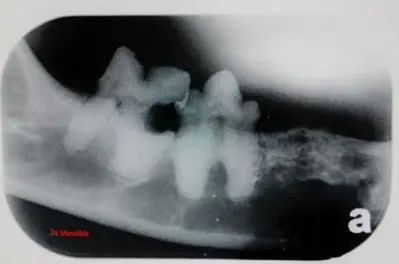

Dogs and cats get periodontal disease much the same as we do!  Since they can’t brush and floss their teeth after every meal, most animals will build up plaque and tartar on their teeth early in life.  We provide thorough dental cleaning services, which include cleaning with an ultrasonic cleaner and hand scaling instruments.  This allows us to fully evaluate the degree of disease and act accordingly.  Many times, though the teeth may appear to be clean, there can be infection, exposed roots, resorbtive lesions, cracked teeth or deep pockets in the gingival margins.  We employ dental radiography to access the roots of the teeth to help evaluate the health of a tooth and determine whether extraction is necessary.  Once the teeth are thoroughly scaled, they are flushed with a disinfectant, polished and give a fluoride treatment.  Dental prophylaxis is performed under general anesthesia and the same equipment and protocols are used as with any surgical procedure to monitor your pet throughout the entire procedure.